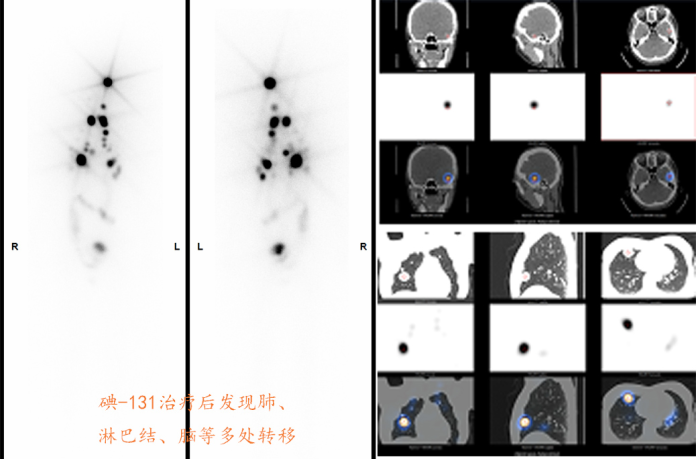

(3)甲状腺癌的治疗手段中,手术是不能替代的,但残留亦是难以避免的,因此术后行核医学的碘-131治疗是进一步的将残留甲状腺清除、减少,从而降低复发与转移的风险,更是对转移灶起到发现与治疗的作用,尤其对于中、高危患者有必要。

甲状腺癌术后碘-131治疗后残留甲状腺的发现及治疗后残留甲状腺清除效果

↓   ↓   ↓

甲术后状腺癌转移灶的发现、治疗后效果